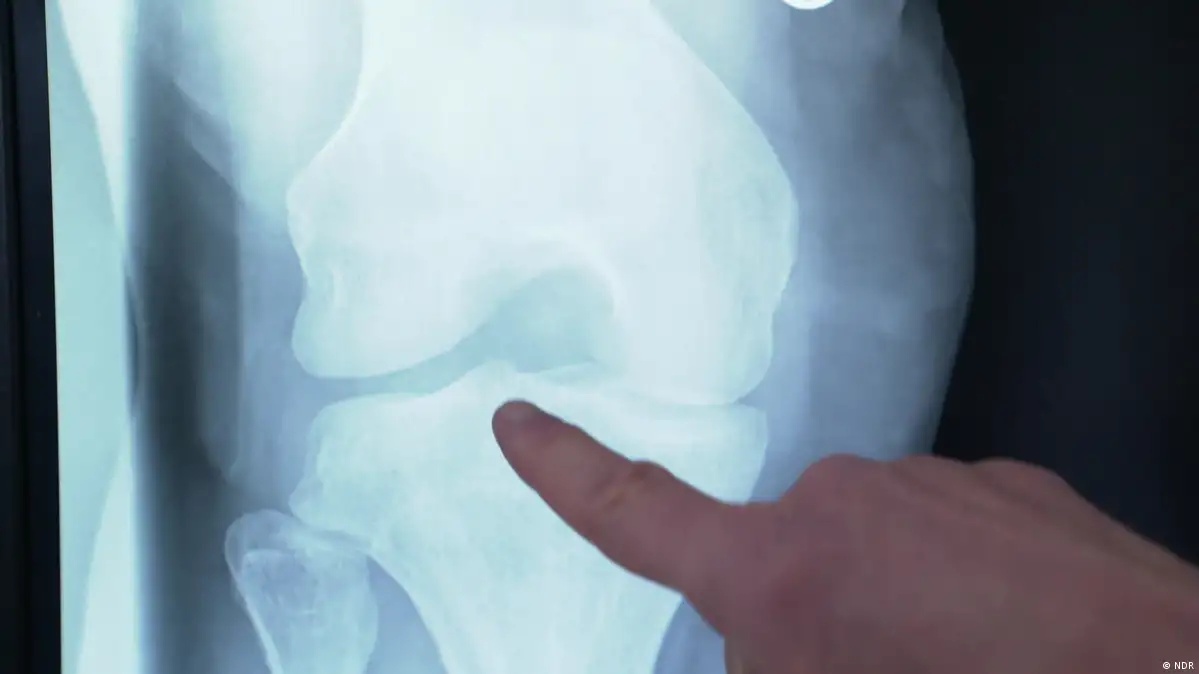

Chronic back or knee pain is often the start of a vicious circle. We move less and that leads to more pain. Exercise therapy can get us moving again — properly!